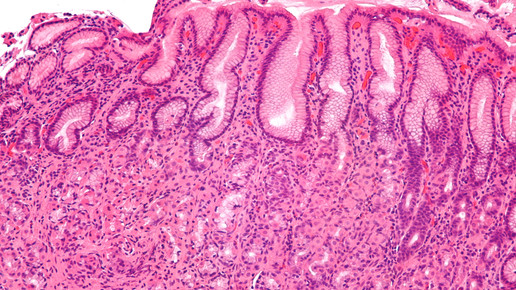

Übelkeit, Völlegefühl, Schmerzen im Oberbauch: Das sind mögliche Anzeichen für eine Entzündung der Magenschleimhaut. Auch Aufstoßen, Appetitlosigkeit und Mundgeruch können darauf hindeuten. Einer der möglichen Auslöser für die sogenannte Gastritis ist eine Infektion mit dem Bakterium Helicobacter pylori, wie das Ärztliche Zentrum für Qualität in der Medizin (ÄZQ) erläutert. Die Bildung von Magensäure wird durch die Bakterien verstärkt und die Schleimhaut dadurch weiter geschädigt. In der Folge können etwa Magen- oder Darmgeschwüre entstehen.

Damit es so weit nicht kommt, sollte man bei entsprechenden Symptomen zum Arzt gehen. Mit einer Magenspiegelung mit Gewebeentnahme sowie einem Stuhl- oder Atemtest lässt sich die Erkrankung nachweisen.